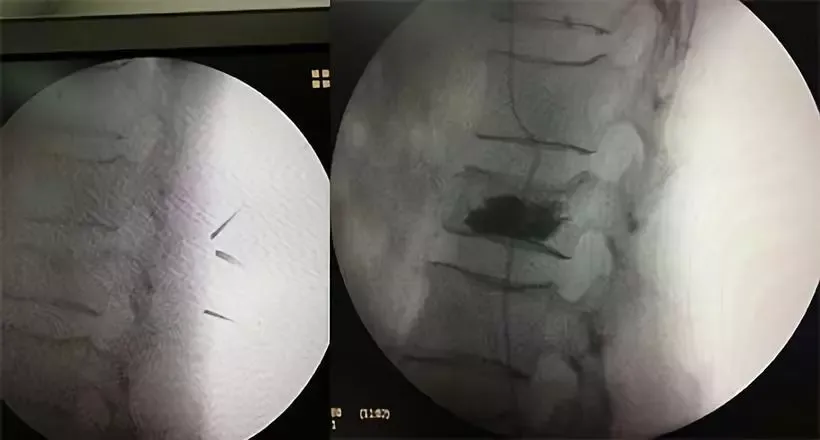

目前,针对脊柱骨质疏松性骨折治疗分为保守治疗和脊柱微创手术治疗,保守治疗需绝对卧床3月,严重影响患者生活质量,同时易发严重感染而危及生命。如果手术治疗,患者年龄偏大,既往高血压病史,长期服用降压药,且心电图回示异常,血钾偏低,基础情况复杂,手术风险较大。但考虑到患者生活质量与恢复情况,在与家属沟通后,决定采用手术治疗。为确保手术成功,科室成立了治疗小组,针对患者病情多次讨论,制定详尽的诊疗计划,并请相关科室协助,排除手术风险。在准备妥当后,由骨伤科副主任、副主任医师田茂兵主刀,主治医师吴文旭、李国栋协助,于8月27日对患者行经皮腰2椎体后凸成形术,手术非常成功,术后临床效果明显,腰部疼痛已无明显感觉,第二日即可下地,老人家高兴地说:“我总算熬出来了,谢谢你们!”。

我院骨伤科自2016年引进经皮椎体后凸成形术(percutaneous kyphoplasty,PKP),已完成数十例该型手术,无1例不良反应,患者术后生活质量明显提高。PKP是经皮椎体成形术的改良与发展,1999年美国研制出一种可膨胀性扩骨球囊(KyphXTM ,Inflatable Bone Tamp),该技术采用经皮穿刺椎体内气囊扩张的方法使椎体复位,在椎体内部形成空间,这样可减小注入骨水泥时所需的推力,而且骨水泥置于其内不易流动。临床应用显示其不仅可解除或缓解疼痛症状,还可以明显恢复被压缩椎体的高度,增加椎体的刚度和强度,使脊柱的生理曲度得到恢复,并可增加胸腹腔的容积与改善脏器功能,提高患者的生活质量。